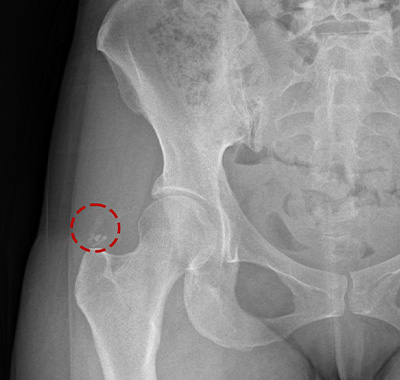

시술 당일 엑스레이를 통해 주사기로

흡입, 제거된 석회를 확인할 수 있습니다.

석회분쇄흡입술 전/후

석회성건염은 칼슘 퇴적물이 관절의 힘줄에 침착되며 염증과 통증을 유발하는 질환입니다.

석회성건염은 어깨, 팔꿈치, 고관절, 무릎, 손목. 발목 등 다양한 관절에 발생합니다.